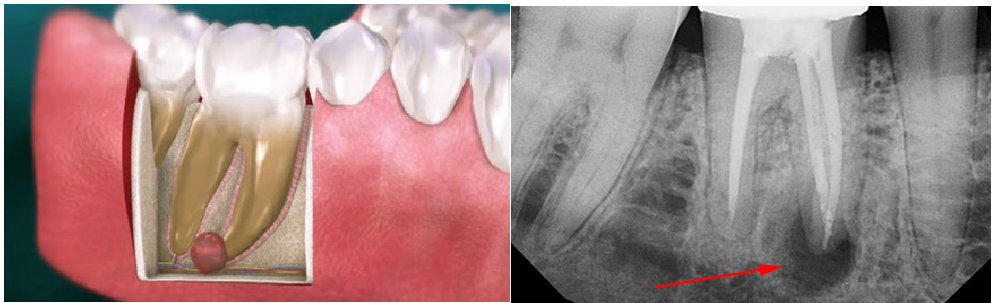

Это доброкачественное полостное образование, заполненное жидкостью или гноем, которое чаще всего формируется у верхушки корня. Это результат хронического воспаления: когда организму не удается полностью победить инфекцию, он «запечатывает» ее в капсулу, чтобы изолировать от здоровых тканей.

Кисты могут достигать размеров более 1 см, оказывая давление на окружающие ткани и разрушая кость.

• рентген-снимок — визуализирует кисту как четко очерченную тень у корня зуба;